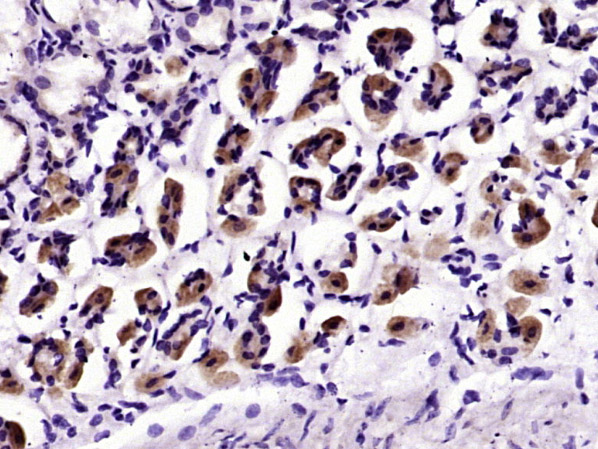

Paraformaldehyde-fixed, paraffin embedded (human pancreatic carcinoma); Antigen retrieval by boiling in sodium citrate buffer (pH6.0) for 15min; Block endogenous peroxidase by 3% hydrogen peroxide for 20 minutes; Blocking buffer (normal goat serum) at 37°C for 30min; Antibody incubation with (MUC5AC) Polyclonal Antibody, Unconjugated (bs-7166R) at 1:200 overnight at 4°C, followed by operating according to SP Kit(Rabbit) (sp-0023) instructionsand DAB staining.